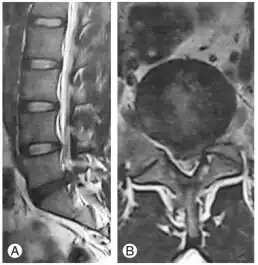

Sagittal and axial MRI scans showed extruded left sided simple L5–S1 lumbar disc herniation

Diagnosis can be made on clinical basis with MRI findings